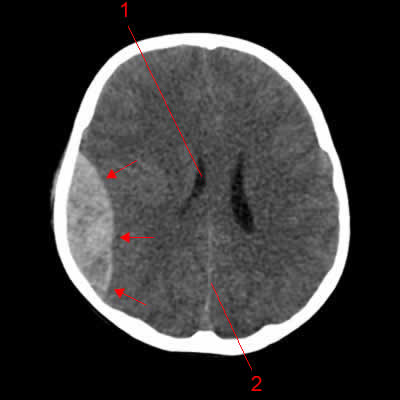

Il est environ 15h00. Je suis transporté aux urgences de la sauvegarde. J’y subi plusieurs examens et rapidement un hématome extra dural est diagnostiqué. Il était vital que je sois opéré rapidement. Des motards arrivent à l’hôpital pour escorter l’ambulance qui doit me transférer vers l’hôpital neurologique de Bron. Florence prend la mesure de la gravité de mon état en voyant l’escorte. Elle qui avait commencé à informer mes proches de l’accident sans les alarmer, doit maintenant annoncer que c’est plus grave. Je suis sédaté et placé dans le coma pour protéger mon cerveau de la pression sanguine de l’hématome. On m’opère vers 18h30. Sans rentrer dans les détails, l’hématome sanguin sur le lobe temporal gauche a été résorbé après l’ouverture d’un volet crânien. Le chirurgien sera très satisfait de cette opération. Mais comme dit Jean Pierre mon cher kiné du centre de convalescence des iris, les chirurgiens sont toujours satisfaits de leur travail !